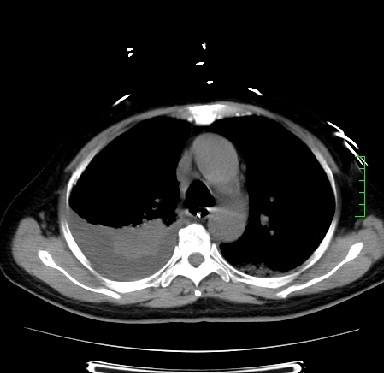

icu病人,几天都没明确诊断。m,76y,咳嗽、咳痰1周,伴气促,右胸痛入院,pe:t38.3c p135 r25 bp135/85。双肺可闻及大量湿罗音,心、腹未见明显异常。诊断:1心衰?2肺部感染?3冠心病?

11号ct

1)两肺感染性病变(右肺下叶肺脓肿可能)。2)双侧胸腔积液,以右侧为甚。

ards,肺感染性病变,右下叶实变,双侧胸腔积液,右侧为著,叶间胸膜积液,右上肺陈旧性tb纤维灶,左室大。

考虑:双肺感染、右肺下叶肺脓肿,双侧胸腔积液,肺水肿.请结合临床.